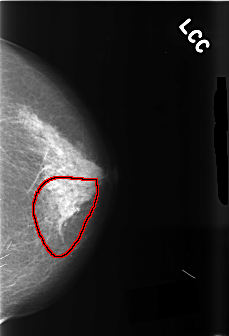

C_0458_1.LEFT_CC

FILE: C_0458_1.LEFT_CC.OVERLAY

TOTAL_ABNORMALITIES 1

ABNORMALITY 1

LESION_TYPE CALCIFICATION TYPE PLEOMORPHIC DISTRIBUTION SEGMENTAL

ASSESSMENT 5

SUBTLETY 5

PATHOLOGY MALIGNANT

TOTAL_OUTLINES 1

BOUNDARY